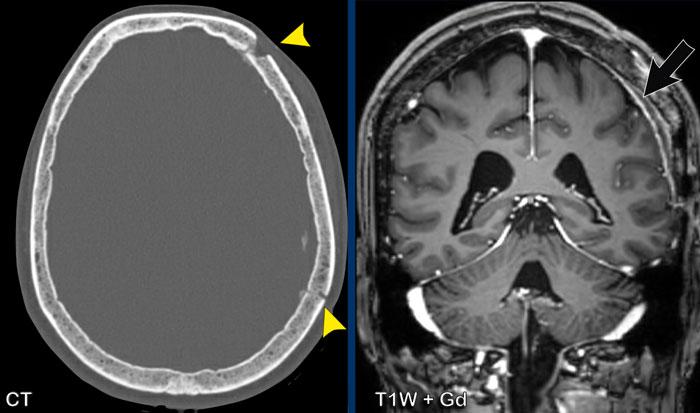

Các hình ảnh này của một phụ nữ 56 tuổi mắc ung thư vú.

Bệnh nhân có tổn thương xương sọ trên xạ hình xương chín năm trước, được cho là di căn xương.

Hiện tại bệnh nhân nhập viện với triệu chứng nôn và đau đầu.

Hình ảnh

Có một tổn thương ngoài trục lớn phù hợp với u màng não.

Có tăng sinh xương sọ rõ rệt và xâm lấn xoang tĩnh mạch dọc trên.

Đây không phải là di căn xương do các dấu hiệu này và thực tế là tổn thương đã hiện diện trong chín năm.

Các hình ảnh này của một nam giới 58 tuổi mắc ung thư phổi.

Có hai tổn thương bắt chước hình ảnh của u màng não.

Tiếp tục xem các hình ảnh theo dõi…

Trên hình ảnh theo dõi sau 2 tháng, tổn thương phát triển đáng kể.

Hiện tại bờ tổn thương không đều.

Đây hóa ra là di căn màng cứng.